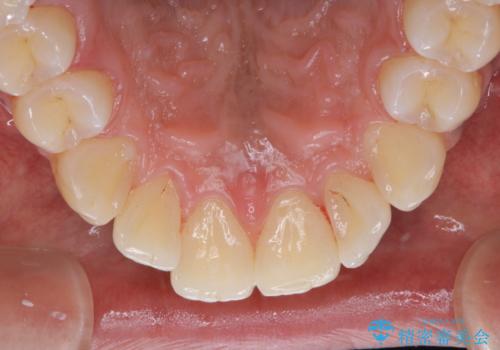

他人から口臭を指摘されて初めてのPMTC

- 他人から口臭を指摘されたので歯のクリーニング希望との事でした。

PMTC60分コースを行いました。

バイオフィルム(細菌の塊)を破壊し、歯の表面をツルツルにすることでお口の中の細菌数を減らし歯周病のリスクが定着するのを防ぎます。更に、歯に新しい汚れがつきにくい状態になります。

歯石除去をすることにより、歯と歯の間に隙間が見られることがあります。

ただし、それは今まで歯石により埋め尽されていた状態だったため、開いた隙間は正常な歯肉の状態です。

PMTCを行うことにより、虫歯・歯周病・口臭予防だけでなくスッキリと爽快感が得られたり、見た目も清潔感のある状態になるため、今後の治療などお口に対するモチベーションUPにも繋がります。